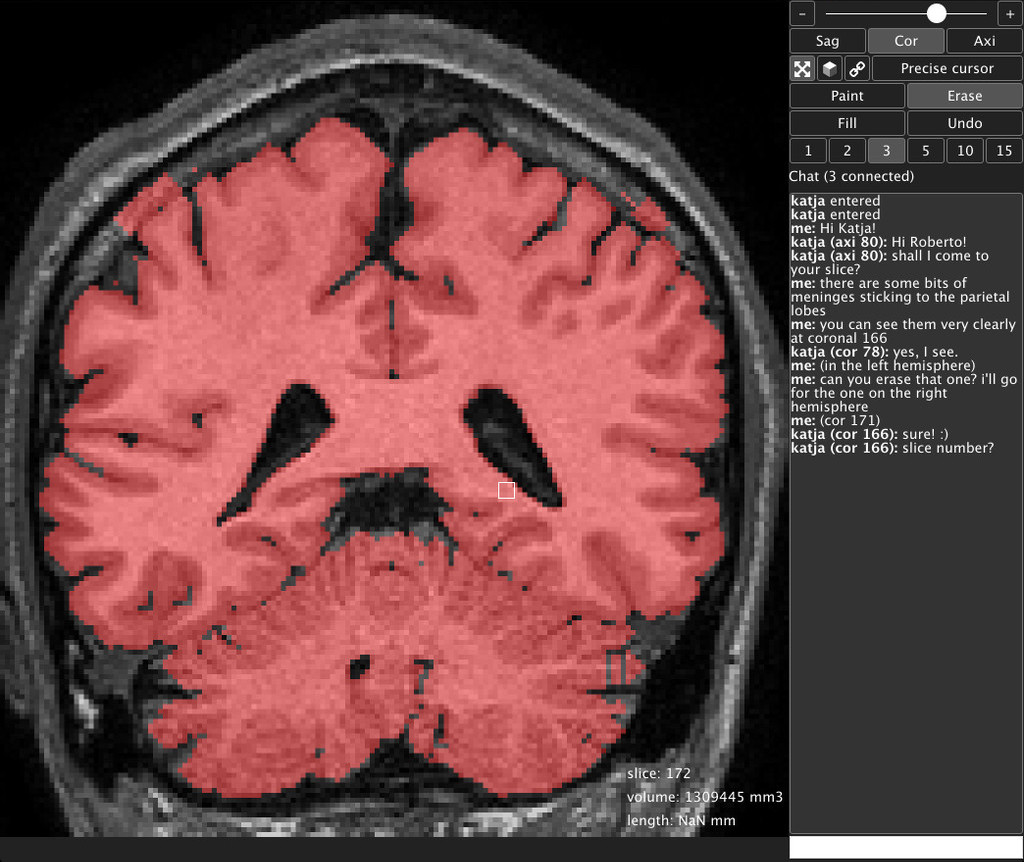

We proposed to develop a collaborative environment that would allow anyone with a web browser to analyse MRI data available anywhere online: Amazon, Figshare, DropBox, Zenodo, GitHub, etc. We presented a prototype of our web app BrainBox for collaborative segmentation.

We had the opportunity to explore the sonification of real-time EEG data, to work together on the segmentation of the brains from our Brain Catalogue, and we had tutorials on brain tractography, functional parcellation of the brain and genomics.

We are currently scanning and processing the collection of vertebrate brains from the Muséum National d'Histoire Naturelle de Paris, and building online tools to visualise and analyse the data, collaboratively.